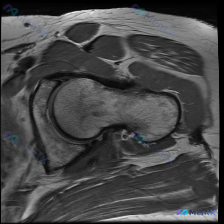

整理了一个髋关节MRI病例,先只放T2冠状位的影像分析。 核心信息: - 右侧髋关节MRI(T2冠状位) - 股骨头内侧近关节面下骨髓区:边界欠清的斑片状低信号影 - 关节间隙、髋臼、周围软组织无明显异常 用户最初问题是“盂唇病变”,但影像的核心发现是骨内异常信号。 大家第一眼看到这个低信号,会优先...

最近看到一个髋关节MRI病例,临床高度怀疑盂唇病变,但单一切面(T2冠状位)影像结果有点意外。先放影像分析的关键信息,大家一起讨论: 影像所见: - 股骨头、股骨颈、髋臼形态正常,皮质连续,骨髓信号无异常 - 关节间隙正常,无狭窄或增宽 - 盂唇结构清晰,信号均匀,未见撕裂、退变或囊肿 - 周围软组...